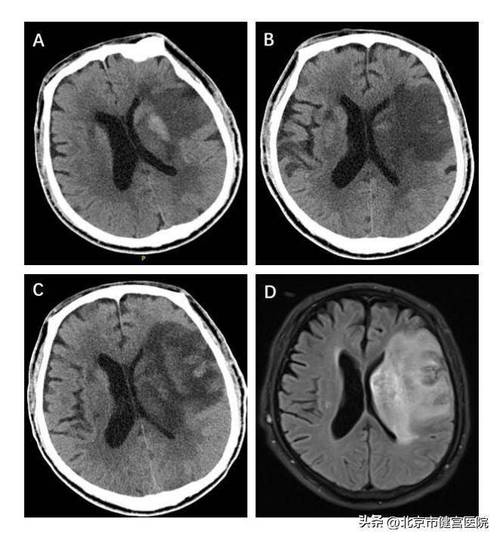

头颅CT通过X射线扫描大脑,生成大脑的横断面图像,当脑梗发生时,核心的病理变化是缺血性脑细胞坏死,这个过程会引发一系列改变,CT影像上主要表现为:

• 通常难以发现:在脑梗发生的最初几小时内,脑组织的密度变化非常细微,普通CT可能完全正常,这是CT检查最主要的局限性。

• 早期间接征象(经验丰富的医生可能会发现)

• 脑动脉高密度征:供应梗死区域的某根大动脉(如大脑中动脉)在CT上呈现出比周围脑组织更高的密度,提示该动脉内有血栓形成。

• 脑沟消失/变浅:局部脑组织因为水肿而轻微肿胀,导致脑沟(大脑表面的沟回)变浅或消失。

• 急性期(6小时 - 3天):

• 密度降低(最典型表现):坏死的脑组织因为细胞水肿和坏死,密度会逐渐降低,在CT图像上表现为低密度灶,这个区域通常呈楔形,其尖端指向血管的走向。

• 占位效应:随着水肿加重,梗死区域周围的脑组织会被挤压,导致中线结构(如大脑镰)移位,脑室受压变形。

• 亚急性及慢性期(3天以后):

• 边界更清晰:低密度灶会变得更加清楚、锐利。

• 脑萎缩:长期后,坏死的脑组织会被吸收,形成囊腔,局部脑组织会萎缩,表现为脑沟加深、脑室扩大。